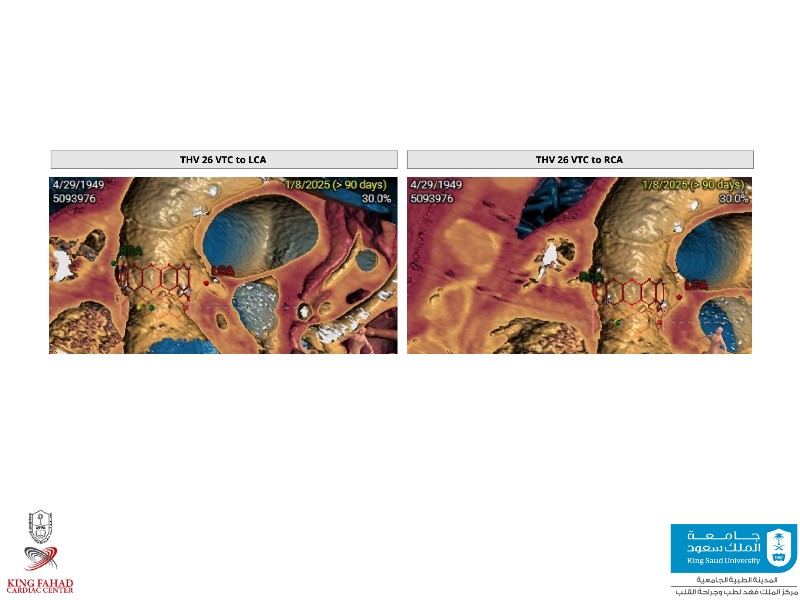

This session helps you anticipate and address complex scenarios such as mitral valve-in-valve, TAV-in-SAV, and valve-in-valve-in-valve procedures. Learn from expert case discussions that explore procedural strategies, technical challenges, and best practices to optimize outcomes in redo structural heart interventions.

- To anticipate and manage second valve scenarios with SAPIEN 3 Ultra RESILIA, including mitral valve-in-valve, TAV-in-SAV, and TAV-in-TAV

- To understand procedural strategies and challenges in complex redo scenarios using SAPIEN 3 Ultra RESILIA